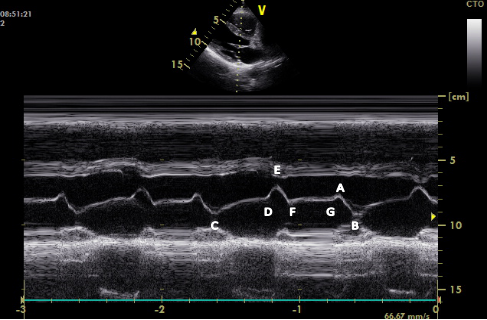

二尖瓣m型超声心动图图中箭头所示两点称为

fg段:代表左心室快速充盈期后,处于相对静止状态的二尖瓣前叶回声曲线